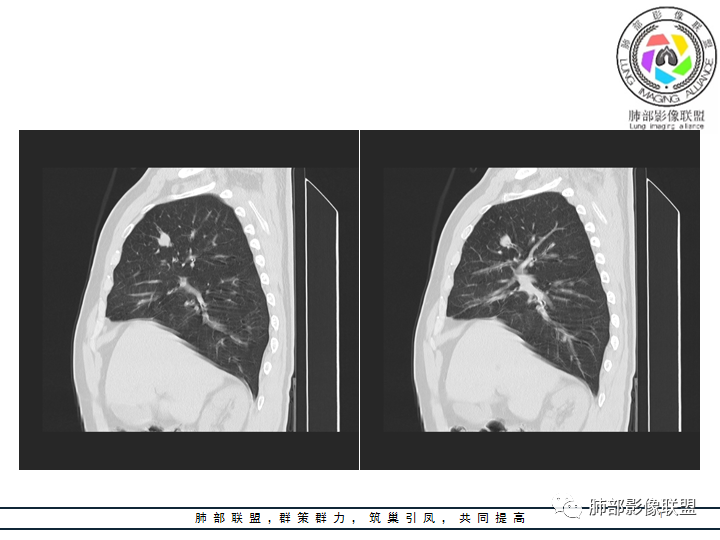

影像资料

老年男性患者,长期吸烟史,没有呼吸系统临床表现。胸部CT示右肺上叶实性密度结节影,密度均匀,未见空洞及钙化,边缘较光整,未见分叶及毛刺。血管影旁现侧出,支气管进入并截断,不均匀强化。

影像上结节影或块影一旦与支气管密切相关(如截断),不支持硬化性肺细胞瘤、错构瘤、孤立性纤维瘤等良性病灶。如此清晰的边缘也不符合一般意义上的炎性渗出。